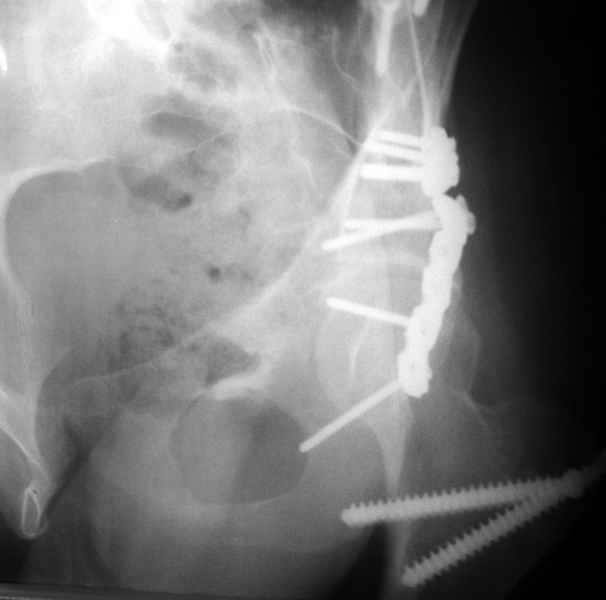

1 закрытая репозиция аппаратом + фиксация через проколы винтами

2 закрытая репозиция передней колонны + открытая задней колонны из задне-неружного доступа

3 открытая репозиция передней колонны из подвздошнго доступа + открытая задней колонны из задне-наружного доступа

4 открытая репозиция из илиоингвинального доступа

5 открытая репозиция из Y образного доступа

Я бы ориентировался на Y образный доступ

или из двух если есть сомнения в целостности задних отделов крыла.

прикладываю схему доступа и случай.

Одним задне наружным переднюю колонну не достать, а илио-ингвинальный более сложный не позволяет контролировать суставную поверхность и трудно управлять задней колонной.